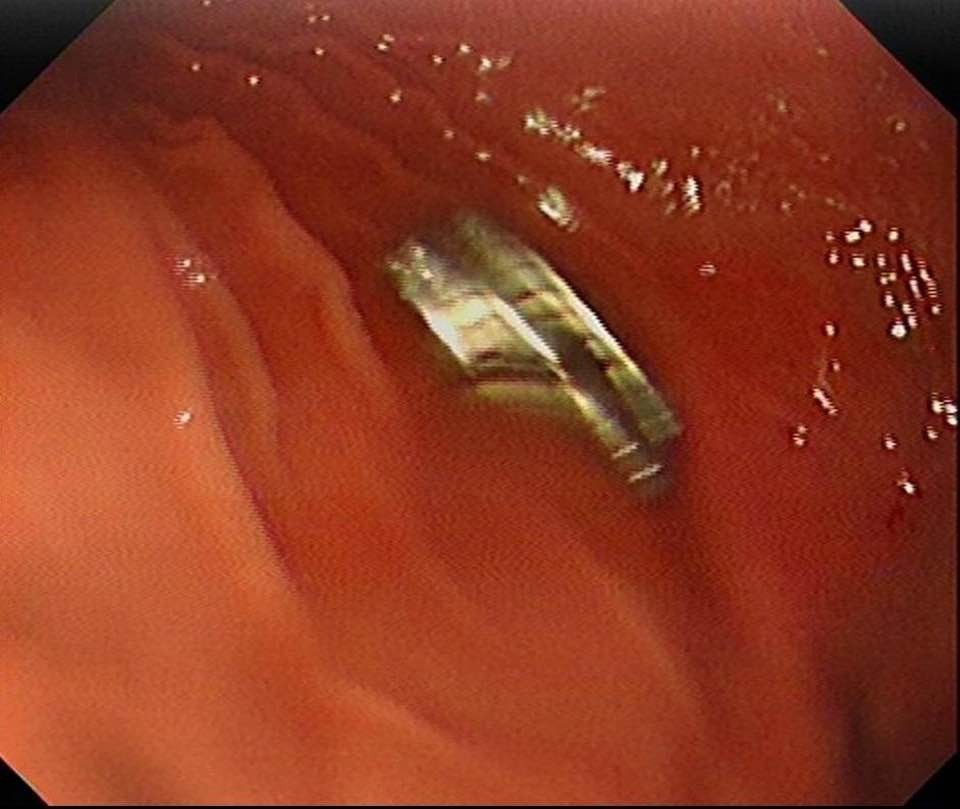

Edinilen bilgiye göre, Erzurum’da bir çocuk evde bulunan 19 tane mıknatısı yuttu. Çocuğun rahatsızlanması sonucu durumu öğrenen aile hastaneye başvurdu. Daha sonra çocuk Elazığ’a sevk edildi.

Fırat Üniversitesi Çocuk Gastroenteroloji Hepatoloji ve Beslenme Bilim Dalı Başkanı Prof. Dr. Yaşar Doğan, çocuk hastanın yemek borusuna yapışmış 19 mıknatısı endoskopik yöntemle çıkardı.

Mıknatıslar uzun süre yemek borusunda takılı kaldığı için yemek borusu ve mide girişinde zedelenmeler olurken, çocuğun sağlık durumunun iyi olduğu ve taburcu edildiği öğrenildi.